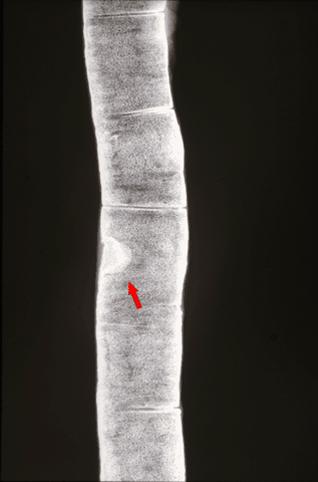

疾病(病理主体)的分类肿瘤样病变/其他

部位(按器官分)小肠/回肠

检查方法X线

肿瘤最大直径10~14

多发性肿瘤(同一器官)